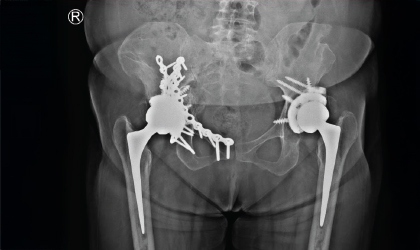

Early Intervention Case Study

Length Restored, Life Restored

This 62 year old driver travelled all the way from his home in Wayanad to have the hip revised.